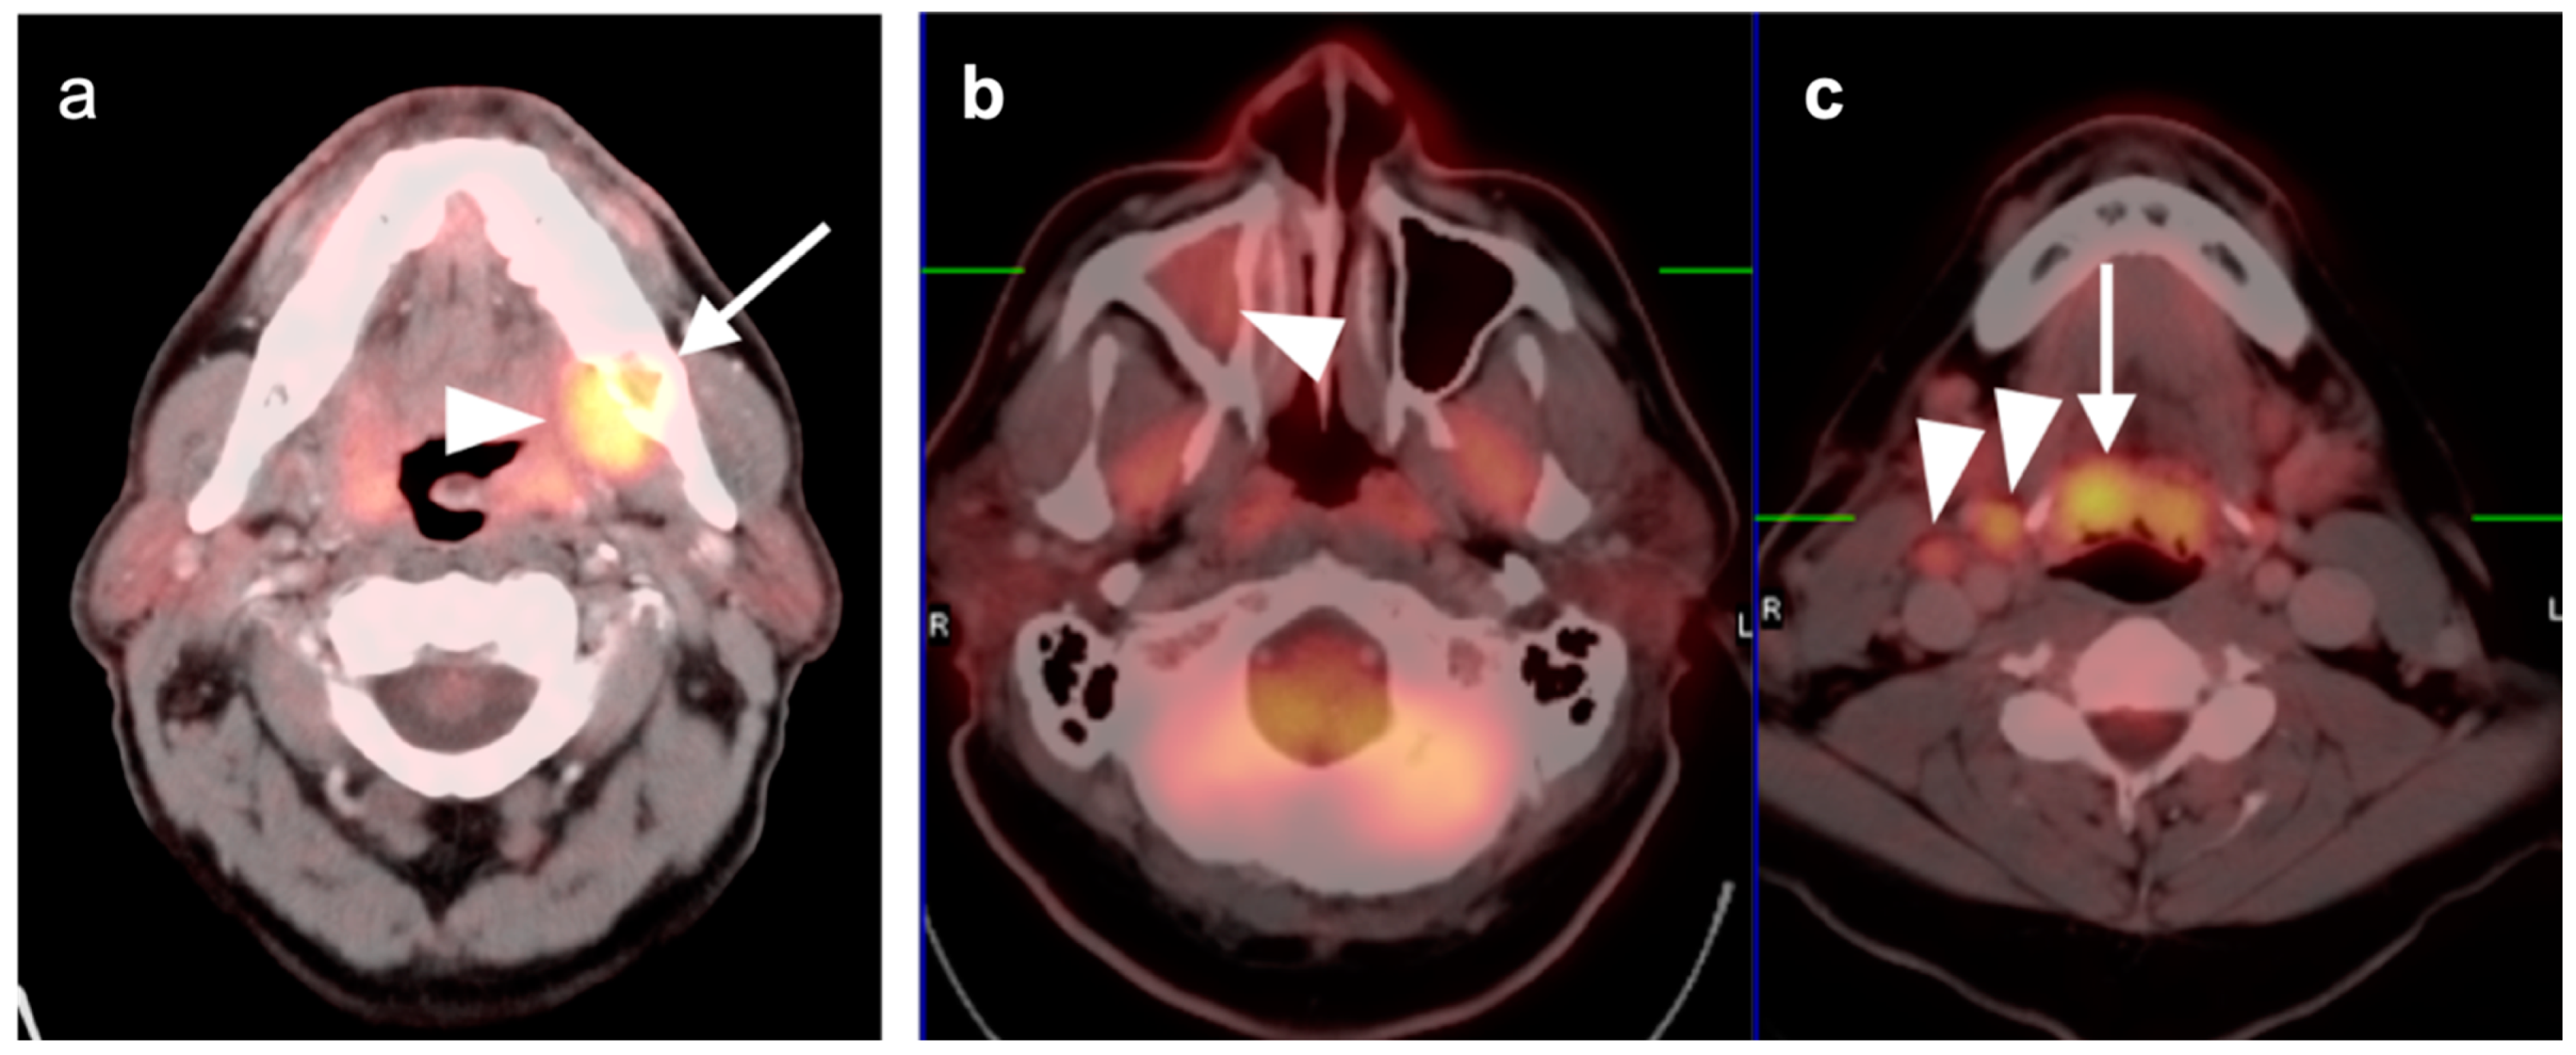

2.4. Sinonasal Tumors

2.5. Major and Minor Salivary Gland, Lacrimal Gland Tumors

- Adenoid cystic carcinoma